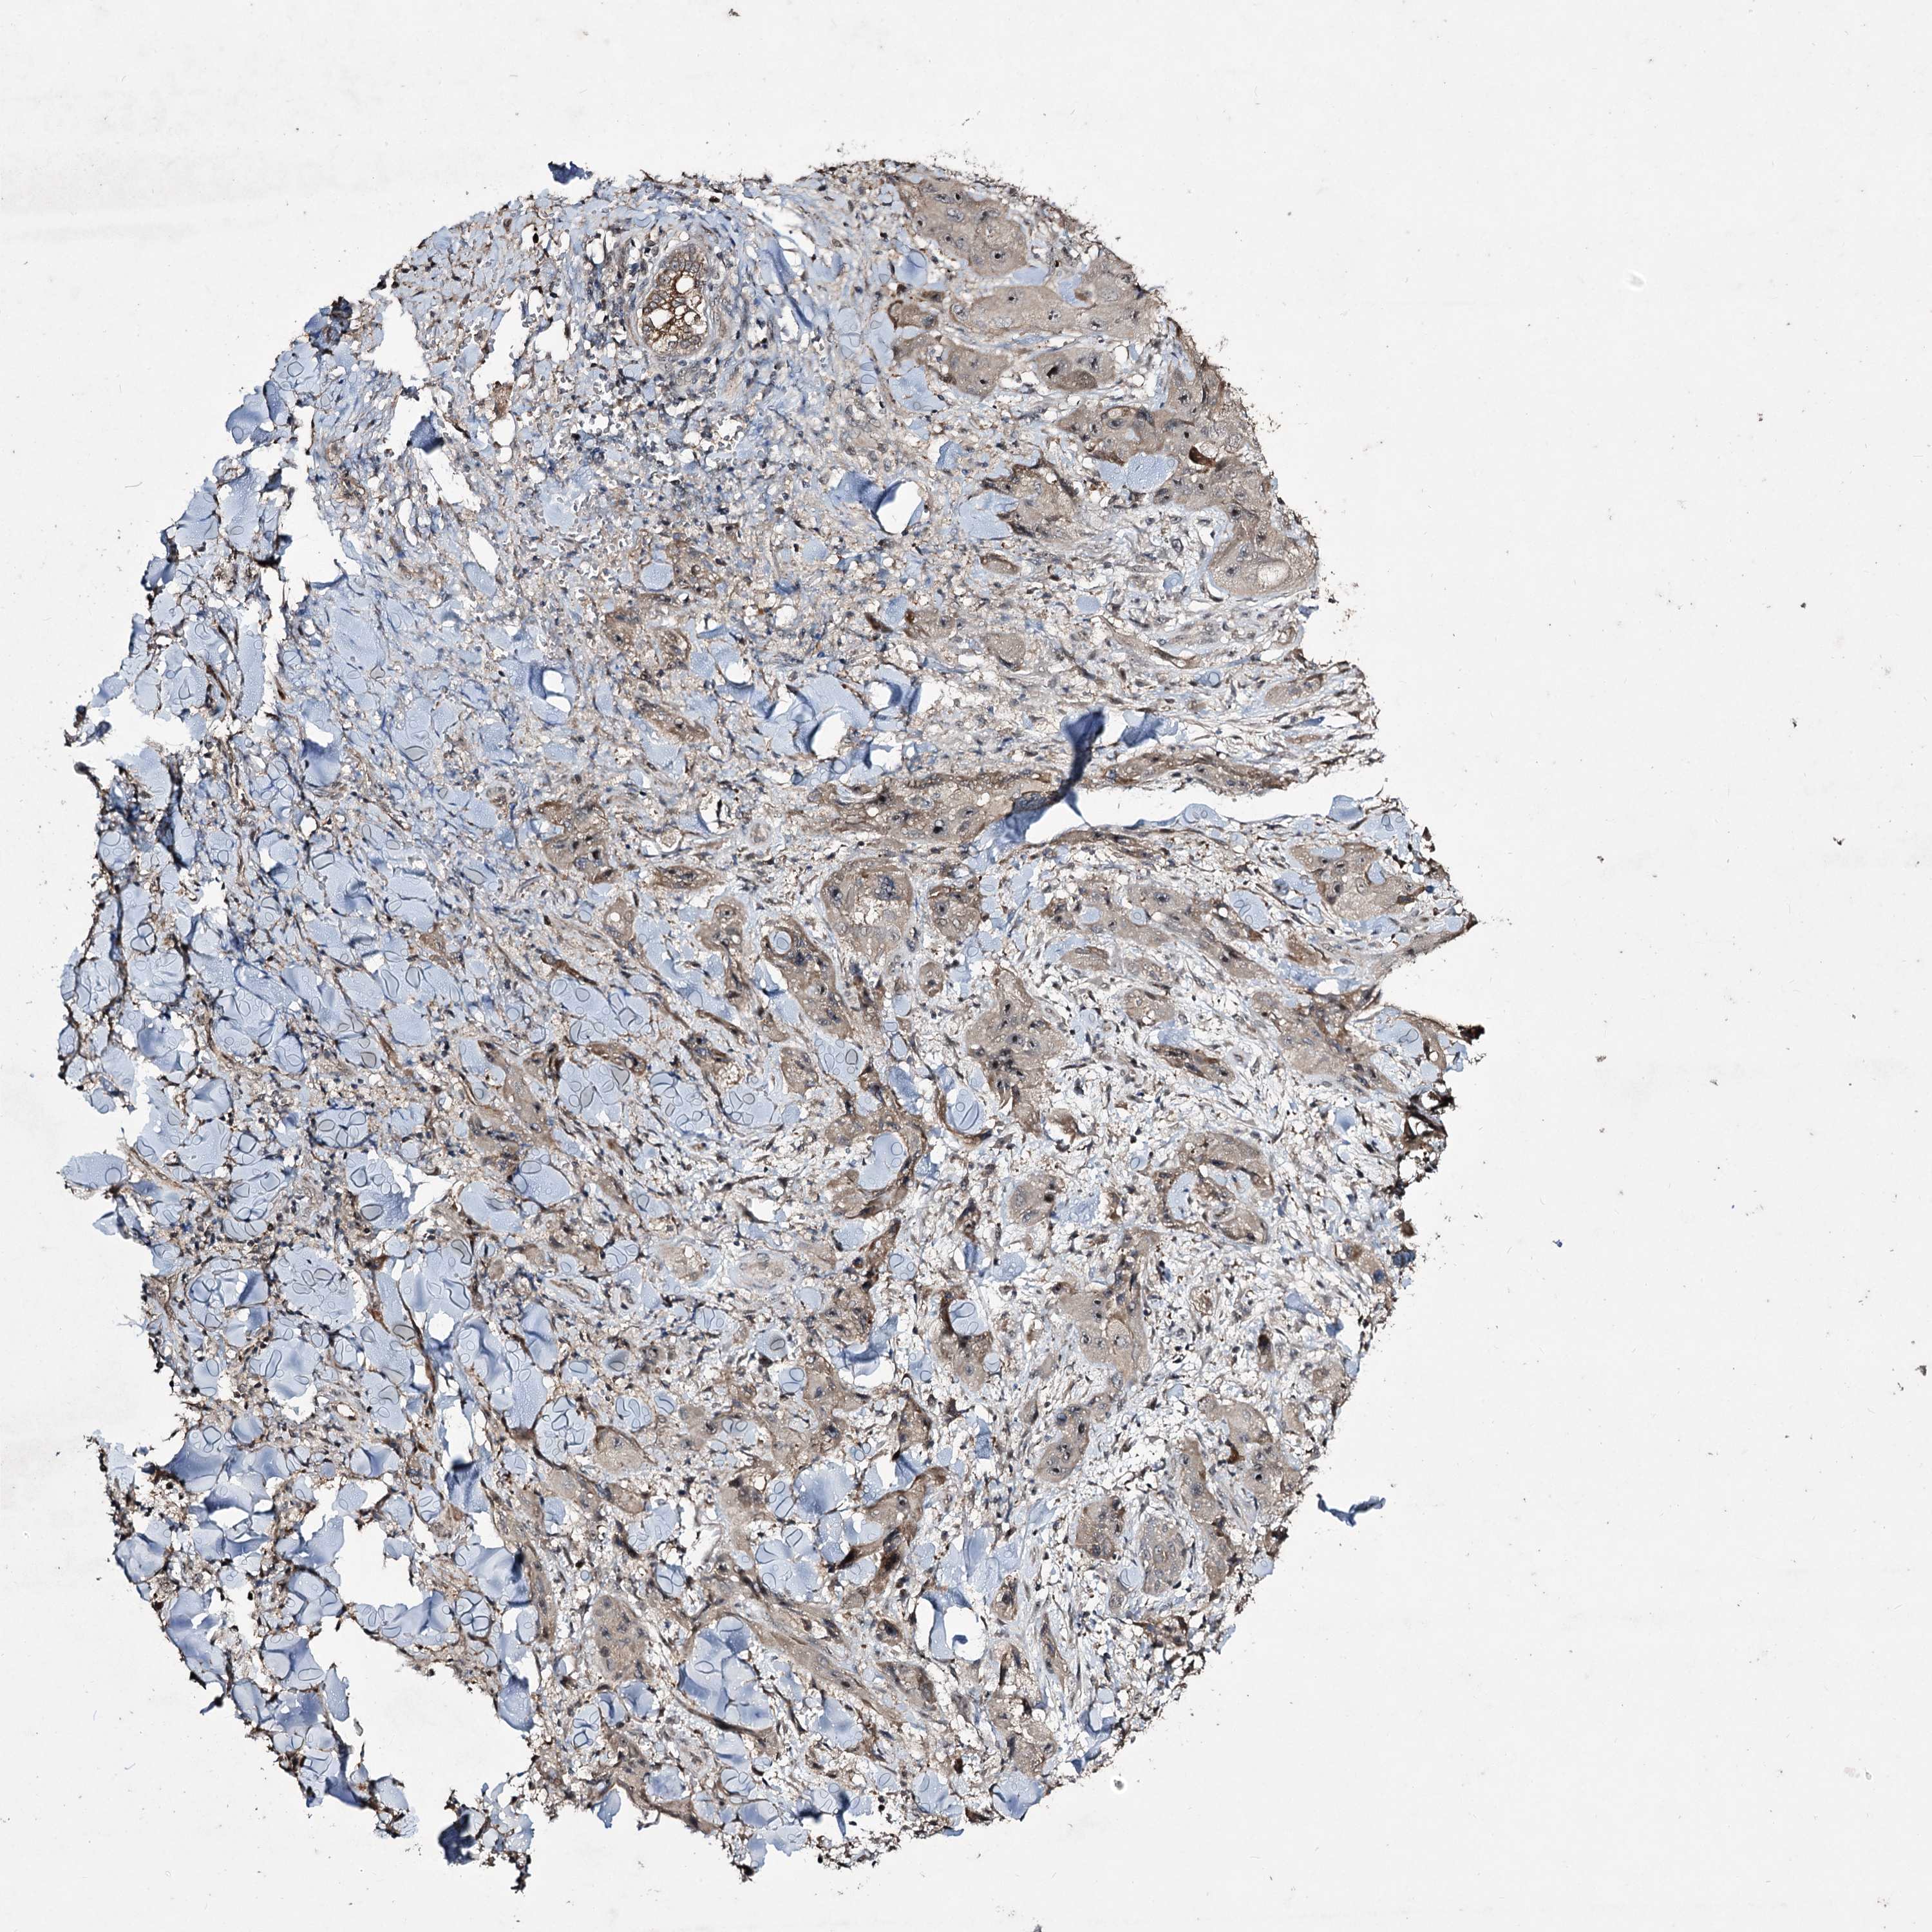

SKIN CANCER - Protein expressioni

A mouse-over function shows sample information and annotation data. Click on an image to view it in a full screen mode. Samples can be filtered based on level of antibody staining by selecting one or several of the following categories: high, medium, low and not detected. The assay and annotation is described here.

Each image is clickable and will lead to virtual microscopy that enables deeper exploration of all samples and also displays staining intensity scores, fraction scores and subcellular localization as well as patient and tissue information for each sample.

Antibody HPA038600

Staining

High

Medium

Low

Not detected

Intensity

Strong

Moderate

Weak

Negative

Quantity

>75%

75%-25%

<25%

None

Location

Nuclear

Cytoplasmic/membranous

Cytoplasmic/membranous,nuclear

Basal cell carcinoma

Squamous cell carcinoma, NOS

Squamous cell carcinoma, metastatic, NOS